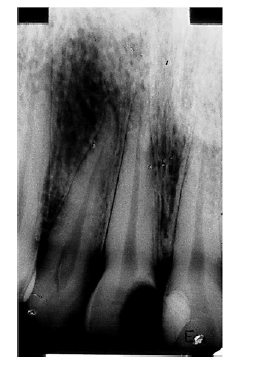

Com base na imagem da radiografia apresentada e nos conhecimentos relativos à histopatologia pulpar e periapical, julgue os itens a seguir.